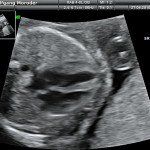

Con l’ecografia transvaginale è possibile vedere dopo circa 3 settimane dal concepimento la camera gestazionale nella cavità uterina. Successivamente è possibile visualizzare l’embrione (3-5 mm.) a circa 6 settimane dall’ultima mestruazione (4 settimane dal concepimento) ed a questo periodo è già visibile l’attività cardiaca fetale Anche i primi dettagli sulla morfologia fetale (polo cefalico, abbozzi degli arti) sono visualizzabili più precocemente con l’ecografia transvaginale, risultando essi visibili intorno a 8-9 settimane.